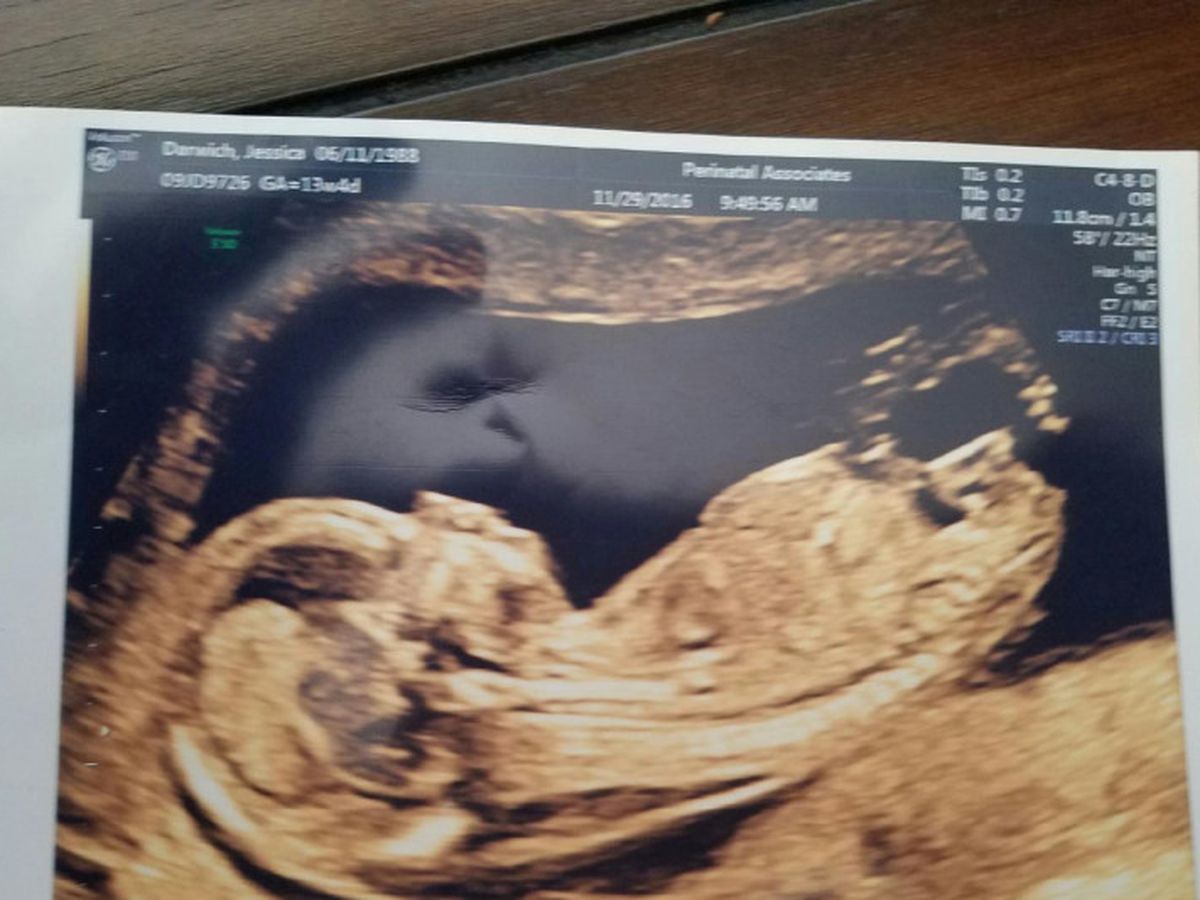

Unfortunately, yesterday…. My love and I found out our new little girl has a rare form of Cystic Hygroma.

This means she has a group of cysts forming around her neck and spine which was caused by an error in the development of the lymph vessels. These vessels carry fats and immune system cells and since they are developing abnormally it has become not only dangerous for her but also for me.